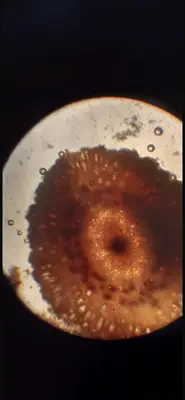

Ginger cross section showing:

Ring of vascular bundles

Fibrous sheath

Yellowish secretory oil cells#1